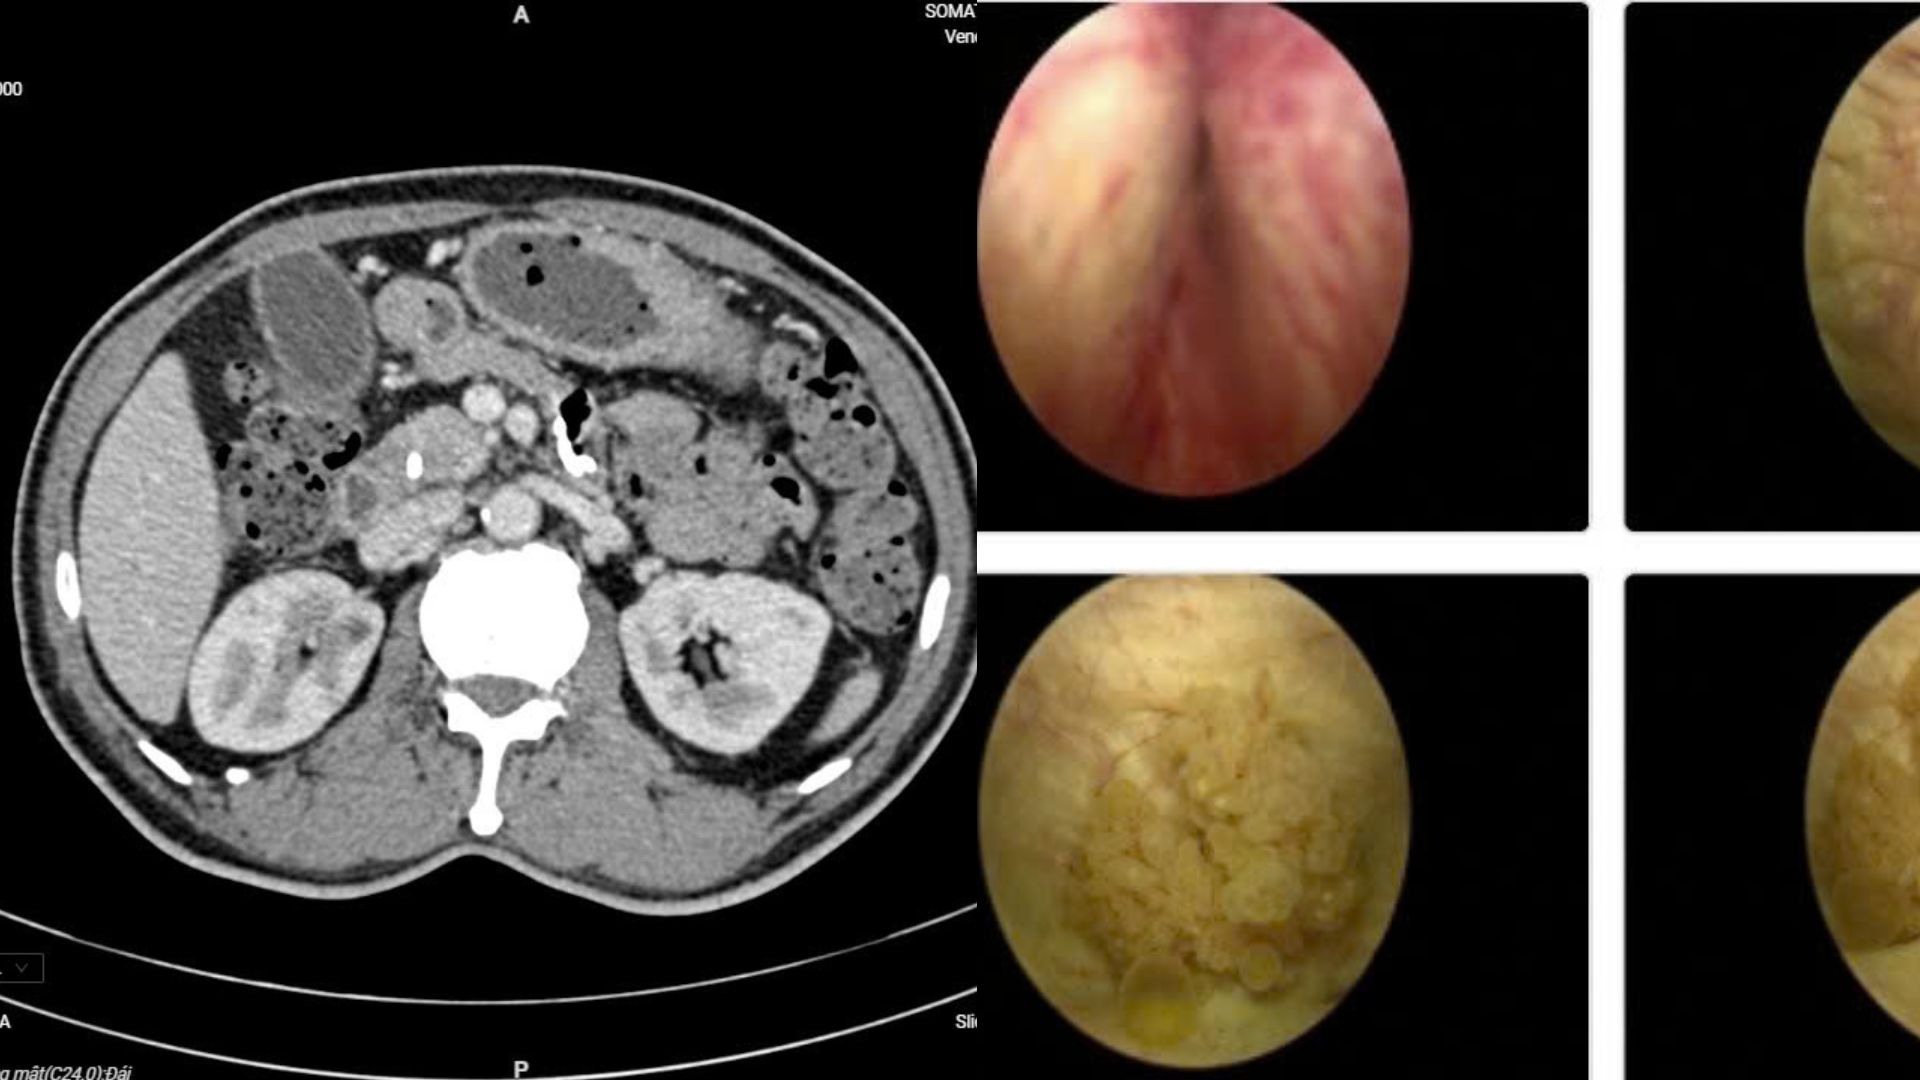

Người bệnh Đ.V.L nhập viện với biểu hiện đau bụng lâm râm kéo dài kèm vàng da nhẹ. Các xét nghiệm chuyên sâu và chẩn đoán hình ảnh cho thấy ông mắc đồng thời ung thư bàng quang và ung thư ống mật chủ – hai bệnh lý ác tính hoàn toàn khác biệt. Điều đáng nói là trước đó, người bệnh gần như không có dấu hiệu đặc trưng nào.

Các chuyên gia đã tổ chức hội chẩn liên chuyên khoa, thống nhất phương án phẫu thuật nội soi đồng thời cả hai bệnh ung thư. Đây là ca bệnh hiếm gặp, bởi việc can thiệp cùng lúc hai cơ quan khác nhau đòi hỏi trình độ chuyên môn cao và sự phối hợp chặt chẽ giữa nhiều chuyên ngành.

Ê-kíp gồm các chuyên khoa Tiết niệu, Gan mật tụy, Chẩn đoán hình ảnh và Giải phẫu bệnh đã phối hợp theo mô hình “teamwork”. Người bệnh được chỉ định cắt u bàng quang qua nội soi ngược dòng và phẫu thuật cắt khối tá tụy bằng nội soi ổ bụng.

Chỉ có 2 dấu hiệu, người đàn ông phát hiện cùng lúc 2 bệnh ung thư- Ảnh 1.

Kết quả bệnh nhân cùng lúc mắc hai căn bệnh ung thư.